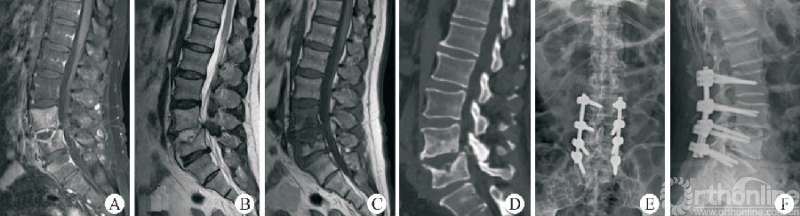

终板塌陷和融合器沉降(图6)是Stand-aloneOLIF的常见并发症,也是导致术后翻修的重要预测因素。融合器沉降与终板强度、手术操作以及解剖稳定性相关。终板硬化及形态平衡能够降低融合器沉降的发生率[36]

图6 OLIF术后融合器沉降

LIU等[37]研究发现,在MRI影像中有Modic改变以及CT影像提示终板硬化的患者终板沉降的发生率明显低于其他患者。术中选择合适的融合器以及良好的脊柱稳定性也有利于降低融合器沉降的发生率[38]。ZHANG等[30]研究利用尸体标本模拟OLIF手术,通过研究生物力学特征、骨小梁微结构损伤等探索融合器与椎体骺环相对大小及位置对终板塌陷及融合器沉降发生率的影响,因此,在Stand-alone OLIF中选择合适的融合器对于减少终板塌陷及融合器沉降至关重要。

FANG等[39]通过构建有限元模型比较Stand-alone OLIF与OLIF联合后路钉棒系统固定两种手术方式后屈伸活动时终板应力等的变化,发现OLIF联合后路钉棒系统可降低屈伸活动时终板所承受的最大应力。术中终板损伤、间隙过度撑开等均会增大融合器沉降的发生风险。